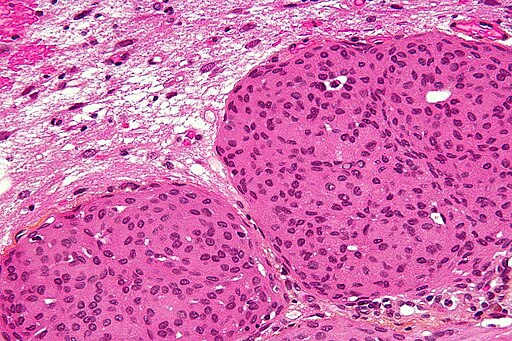

Microfotografie histopatologică (colorație H&E) a unui meningiom atipic (OMS gradul II) cu invazie cerebrală. Celulele tumorale formează „whorluri” caracteristice (corpurile psamomatoase pot fi vizibile ca depozite calcice). Spre margine se observă țesut cerebral invadat (în dreapta imaginii). – Nephron, CC BY-SA 3.0 <https://creativecommons.org/licenses/by-sa/3.0>, via Wikimedia Commons

Examenul histopatologic este necesar pentru confirmarea diagnosticului şi stabilirea gradului tumorii. La meningioamele de grad II şi III se observă anomalii celulare mai evidente (mitoze multiple, invazie cerebrală, pleomorfism) în comparaţie cu formele benigne en.wikipedia.org.

În plus, clasificarea OMS din 2021 a introdus criterii moleculare: de exemplu, prezența mutațiilor în promotori telomerazici (TERT) sau ștergerea genelor CDKN2A/B poate urca un meningiom în gradul III indiferent de aspectul histologic pubmed.ncbi.nlm.nih.gov.